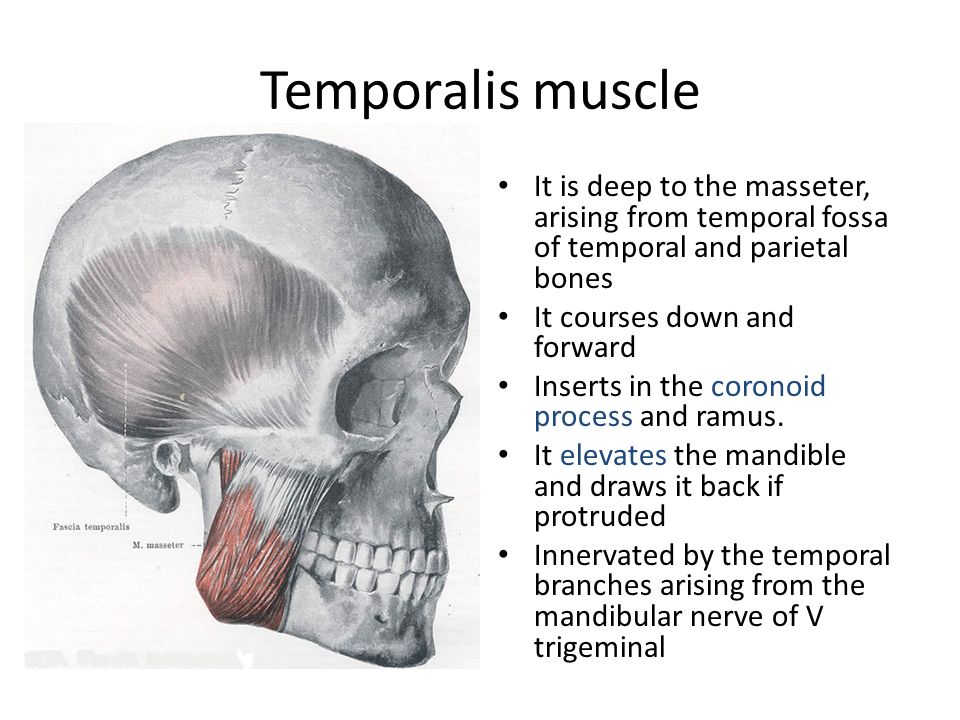

Анатомические особенности: фотографии ямок черепа, височной и подвисочной крылонебной